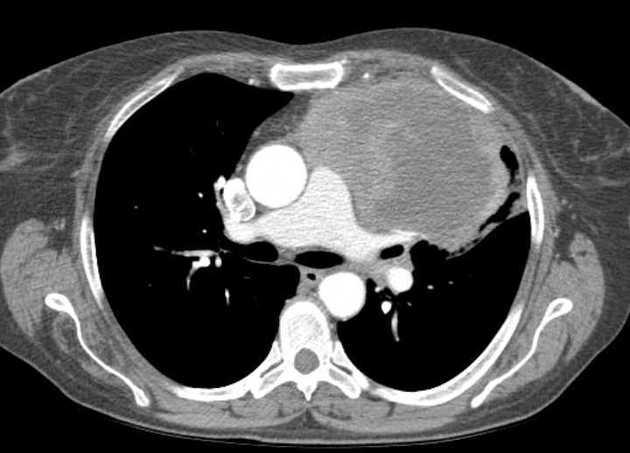

Nốt phổi là gì? Nguy cơ ác tính và lộ trình theo dõi an...

Giải thích nốt phổi dễ hiểu cho cộng đồng: phân loại đặc, kính mờ, bán đặc; nguy cơ ác tính theo kích thước và bờ; khi nào cần chụp PET CT, sinh...